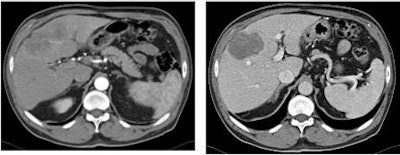

| Chart shows contrast density of normal liver tissue in the arterial phase. There was a statistically significant increase of density of normal liver parenchyma in the arterial phase of imaging using the highest concentration of Iomeprol (p = 0.012). The ANOVA test procedure was used for statistical analysis. Chart courtesy of Dr. Renate Hammerstingl. |

The results showed that the contrast density of normal liver parenchyma was 61.3, 64.8, and 72.7 HU for Iomeprol 300, 350, and 400 (p = 0.01), respectively, in the arterial phase. "There was a significant trend toward improved contrast using higher concentration in the arterial-phase imaging," Hammerstingl said.

In addition, the median contrast density of tissue surrounding lesions tended to be higher for Iomeprol 400 than for the other groups, both at the arterial (74 HU versus 64 and 66 HU) and portal-venous phases (113 HU versus 99 and 102 HU).